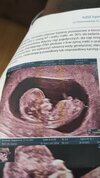

Jestem już po badaniach ale ulga. Wszystko wporzadku l. Bardzo się cieszę według USG 11+3 termin porodu jednak na 8.05

• IMG-20211019-WA0007.jpeg

IMG-20211019-WA0007.jpeg

1,4 MB · Wyświetleń: 127